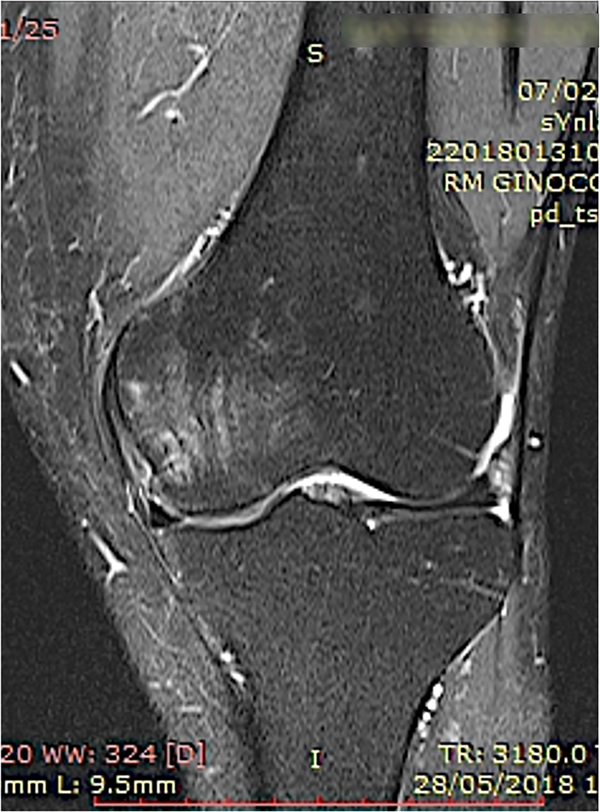

Un estudio clínico reciente concluye que el aumento biológico del hueso subcondral mediante esta técnica resultó en una reducción significativa del dolor y una mejor función articular con resonancia magnética que muestra la resolución de las LMO a los seis y doce meses de seguimiento (figs. 7 a 10).

Figura 7: Un ejemplo de lesión del hueso subcondral en el cóndilo femoral medial de la rodilla tratada con osteocoreplastia. Pretratamiento, vista coronal de la resonancia magnética de la rodilla.

Figura 9: Un ejemplo de caso de lesión del hueso subcondral en el cóndilo femoral medial de la rodilla tratada con osteocoreplastia. Dos meses después del tratamiento, vista coronal de la resonancia magnética de la rodilla.